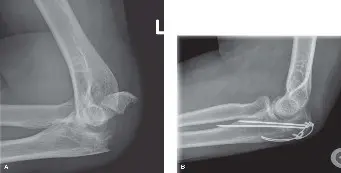

التصوير الشعاعي لتأكيد التشخيص

الأشعة السينية (X-rays):

- الصور الأمامية الخلفية (AP) والجانبية الحقيقية (True Lateral): هذه هي الصور الأساسية والضرورية. الصورة الجانبية الحقيقية حاسمة لتقييم الإزاحة، ووجود أي "درجة" (Step-off) في السطح المفصلي، وشكل الكسر.

- الصور المائلة (Oblique Views): يمكن أن تكون مفيدة لتحديد خطوط الكسر بشكل أفضل، خاصة في الأنماط الأكثر تعقيدًا.

- تساعد الأشعة السينية في تصنيف الكسر (مثل تصنيف مايو) بناءً على الإزاحة والتفتت واستقرار المرفق.

التصوير المقطعي المحوسب (CT Scan):

- يوصى به بشدة في حالات الكسور المفتتة، أو تلك التي تشمل السطح المفصلي بشكل كبير، أو عند الاشتباه في كسور أخرى مصاحبة (مثل كسور الناتئ الإكليلي).

- يوفر التصوير المقطعي معلومات مفصلة حول اتجاه الشظايا العظمية، وتطابق السطح المفصلي، ومخزون العظام المتاح. هذه المعلومات لا تقدر بثمن في التخطيط للجراحة وتحديد الاستراتيجية الجراحية المثلى.

من خلال هذا التقييم الشامل، يمكن للأستاذ الدكتور محمد هطيف وفريقه تحديد نوع الكسر بدقة، ودرجة إزاحته، ومدى تأثيره على السطح المفصلي، مما يمكنهم من وضع خطة علاجية فردية ومناسبة لكل مريض، سواء كانت جراحية أو غير جراحية.